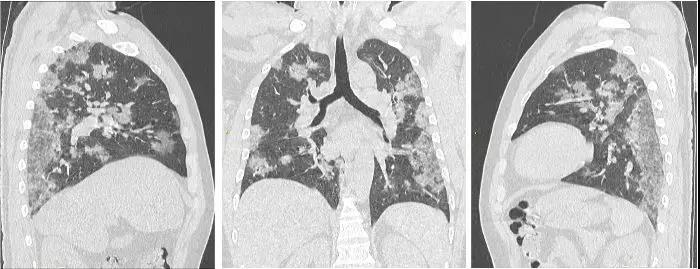

新型冠状病毒感染的肺炎CT图像

新型冠状病毒感染的肺炎CT图像

新型冠状病毒感染的肺炎治疗前后CT图像对比

1、检出率高:因新冠肺炎影像表现早于临床,因此影像学检查是临床前期筛查具有不可替代的作用。

2、快速评估治疗疗效:在临床治疗中, 进行CT检查, 有利于准确判断肺部病变类型、程度、范围以及变化情况。

3、为治愈及出院主要指标之一:核酸阴性CT阳性患者或需要继续留观。

李云启介绍,新型冠状病毒肺炎早期呈现多发小斑片影,以及间质小条索状改变,以肺外带明显。进而发展为双肺多发磨玻璃影、浸润影及网格状纤维化改变。严重者可出现肺实变,甚至机化样改变。虽然肺部CT可能出现“同影异病”的情况,也不能作为核酸检测的替代品确诊新型冠状病毒肺炎,但面对核酸检测条件不允许、疑似病例难以确诊的状态,CT 检查可作为强有力的补充手段进行查漏补缺、防微杜渐,从而尽快找到更多疑似病例和密切接触者进行隔离。寿光市中医医院影像中心拥有全球领先的美国GE公司生产的512层Revolution CT,GE Revolution CT作为美国全进口超高端医疗影像设备,具有扫描速度快、辐射剂量低、图像质量高等多方面等特点,尤其是在肺部扫描、心脏冠状动脉及全身血管联合成像上有无可比拟的优势。